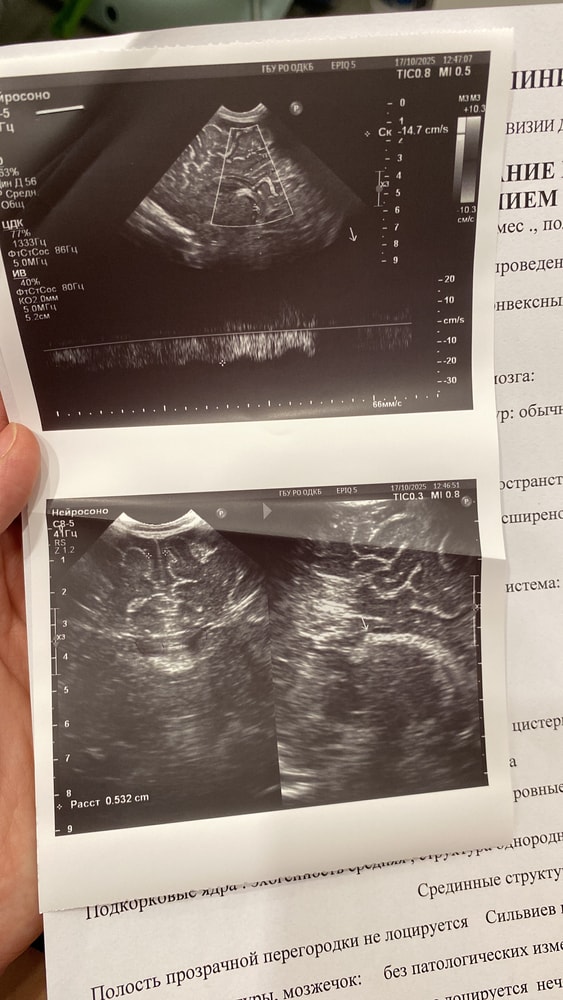

Анализы и их результатыДобрый день. Прошу дочитать до конца и помочь, если у кого была такая ситуация. Мама впервые, ребёнку 3 месяца. Прошли нейросонограмму в детской больнице по месту жительства и поехали на консультацию к неврологу в детскую областную больницу нашего города, так как в нашей поликлинике невролога не было. Причина посещения- поворачивает голову постоянно вправо, как бы не клала, не заинтересовывала игрушками, даже ночью ему постоянно голову поворачивала в другую сторону, все бестолку. И плюс начали закрадываться опасения, что плохо держит голову. По НСГ небольшая псевдокиста, увеличены боковые желудочки. Я уже почитала, что так у многих детей и к году обычно рассасывается само. В общем попали к неврологу, при осмотре было сказано, что плечи в тонусе, синдром короткой шеи, левые мышцы слабее правых, и бонусом ноги в тонусе. Поставили его на ноги, опора есть, но пальцы не разжимает на ногах. А когда тянули за ручки, он не подтягивался вслед, голова так и оставалась висеть. Голову держит плохо, 10 минут не выдерживает лежать на животе, потом роняет голову и начинает заливаться плачем. В общем отправили нас на повторную НСГ строго в областной, ибо невролог доверяет только их результатам, наша НСГ ей «не подошла», и плюс сделать глобальную электромиографию только в определенном центре и только у определенного врача. Ну, делать нечего, сделали, ниже прикреплю фото. В целом невролог не плохой, но вот уж очень смущают меня назначения, которые она выписала. Может кто был в похожей ситуации, какой курс лечения все таки выбрать? Однозначно пойду за 3 мнением к другому неврологу, не хочется 3 месячного ребёнка пичкать препаратами. Я вообще думала только массажем да электрофорезом обойдется